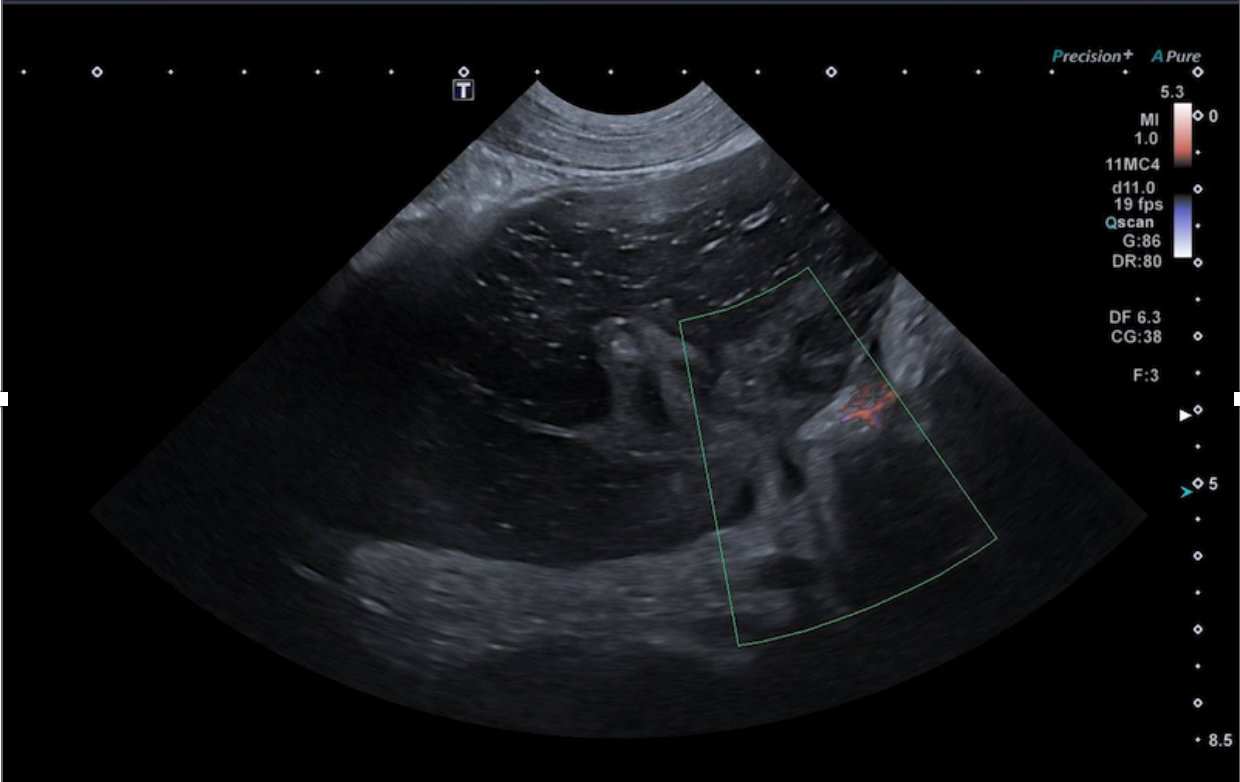

• Sémiologie échographique du tube digestif : signes clés et interprétation.

• Études de cas cliniques vidéo : identification, description, synthèse des anomalies digestives et diagnostic différentiel.

• Sémiologie échographique du pancréas et des surrénales.

• Études de cas cliniques vidéo : analyse, description, interprétation des lésions et élaboration d’un diagnostic différentiel.